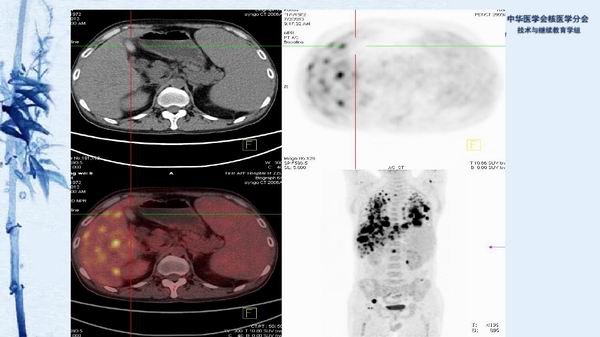

病例49:PET-CT显像诊断淋巴瘤相关噬血细胞综合征一例-【CSNM继教学组】程兵 郑州大学第一附属医院